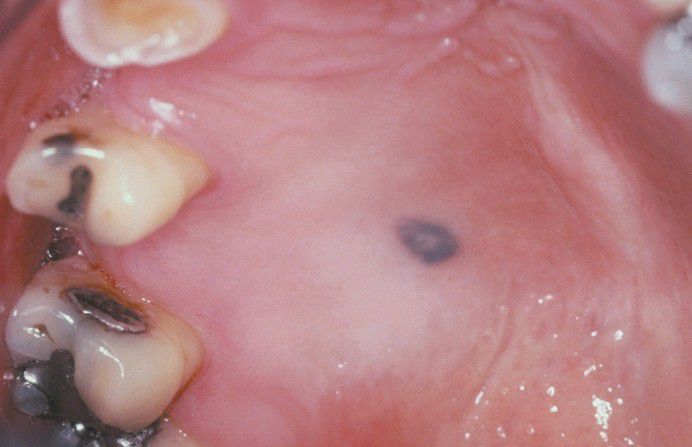

Blue Nevus

A well-circumscribed, deep-blue macular lesion is seen on palatal mucosa.